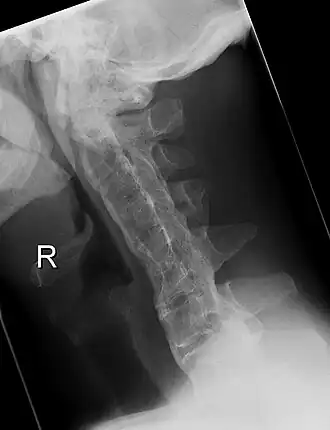

Röntgenfoto van de halswervelkolom met de ziekte van Bechterew in een ver gevorderd stadium. Duidelijk is te zien dat de wervels aan elkaar zijn vastgegroeid, de zogenaamde 'bamboo-spine'.

De wervelkolom kan na verloop van tijd in een benige zuil veranderen. Dit geeft op een röntgenfoto uiteindelijk een karakteristiek beeld, de zgn. 'bamboo-spine'. Daarom moet iemand met deze ziekte dagelijks oefenen om de rug zo veel mogelijk beweeglijk en in ieder geval recht te houden. Gebeurt dit niet, dan zullen de meeste lijders uiteindelijk geheel kromgroeien, waardoor ze op latere leeftijd nog slechts met moeite naar voren kunnen kijken.